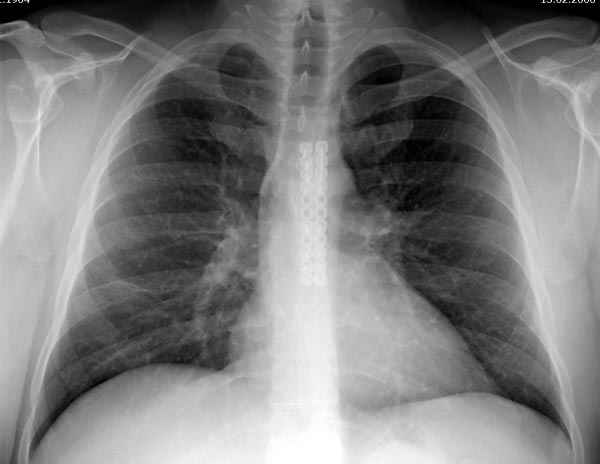

Глубокоуважаемые коллеги, Обратились за советом коллеги из соседней больницы. Мужчина 30 лет, в автоаварии ударился грудью об руль. После травмы 3 недели. Определяется отчетдивая подвижность на месте перелома. Снимок в приложении. Пока обсуждали варианты - LCP (какую?) или спицы. Открывать зону перелома или нет? Что посоветуете?

При переломах грудины со смещением как правило оперируем. В качестве фиксатора используем рекон. LCP, доступ простой, с репозицией проблем не возникало. Для сверла, что бы не провалиться в средостение, используем ограничитель.